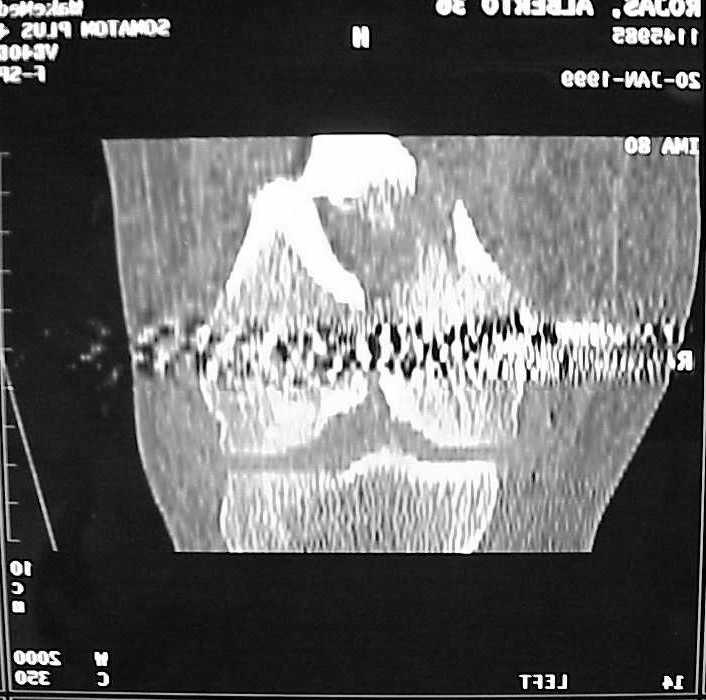

So I think a TAC of the knee could be useful.

A CT and knee xrays would help identify lateral condyle comminution and/or a "hoffa fragment" of the posterior condyle. I am concerned that the lateral cortex is not sufficient to give purchase for a retrograde IMN. blocking screws could improve this as a possibility. A long blade or LISS if avaible would be my secondary choices. Good luck. Any chance you can get these cases transferred earlier when it

Насчет стабильности для ранней нагрузки, конечно, сомнительно, но при таком повреждении ранняя нагрузка противопоказана в любом случае. Для ранних движений Должно хватить. Снимки в следующем сообщении.

воспользовались для репозиции, см. приложение.